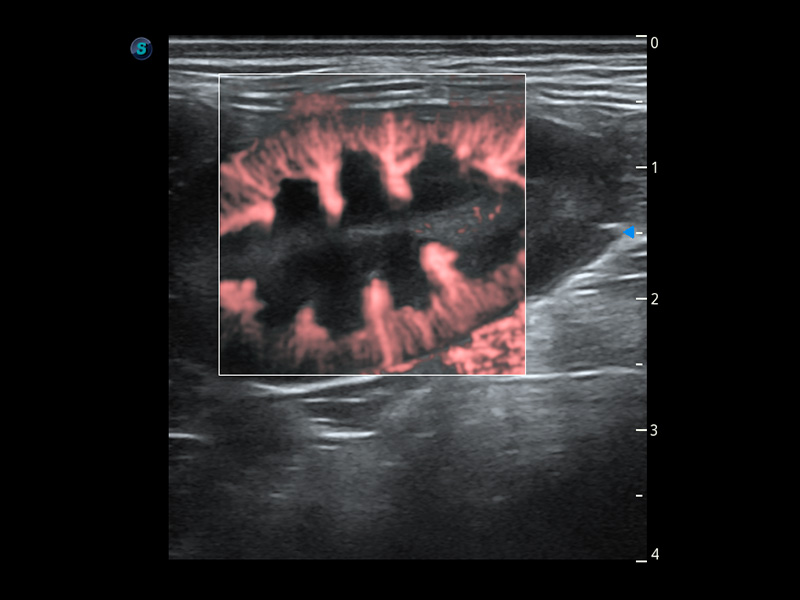

SR Flow 高分辨率血流成像

能够清晰显示细小、低速血流图像,获取传统彩色多普勒技术难以得到的细节和信息。

(犬)肾脏血流